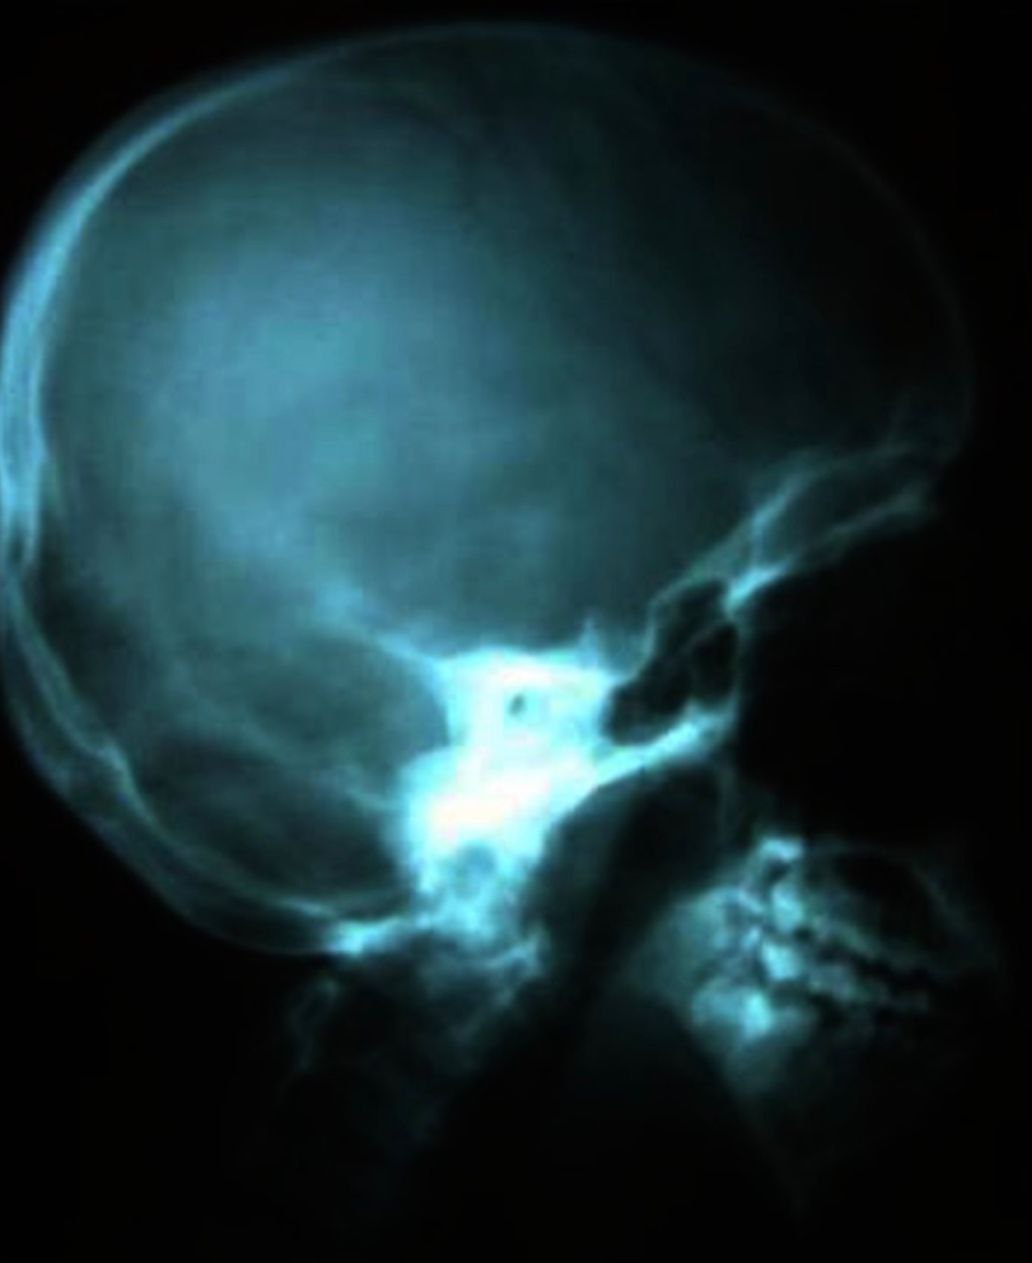

Diagnostic Images & Radiographs

Lateral skull revealed prominent antigonial notch and anterior open bite.